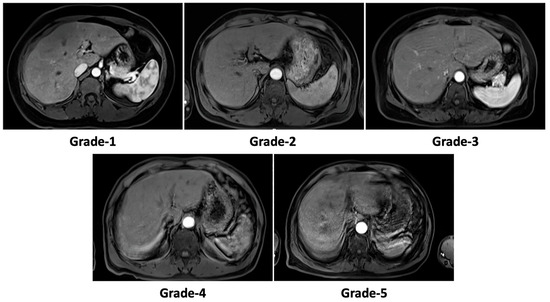

2.3. Motion Artifact Grading

| Total (n = 474 examinations) | |

| Before correction | 2.9 ± 1.3 * |

| DR-CycleGAN | 2.0 ± 0.6 * |

| Cycle-MedGAN V2.0 | 2.4 ± 0.9 * |

| Motion artifact grade-1 (n = 60 examinations) | |

| DR-CycleGAN | 1.0 ± 0.0 |

| Cycle-MedGAN V2.0 | 1.0 ± 0.0 |

| Motion artifact grade-2 (n = 157 examinations) | |

| DR-CycleGAN | 1.9 ± 0.3 |

| Cycle-MedGAN V2.0 | 2.0 ± 0.4 |

| Motion artifact grade-3 (n = 110 examinations) | |

| DR-CycleGAN | 2.1 ± 0.5 # |

| Cycle-MedGAN V2.0 | 2.4 ± 0.6 |

| Motion artifact grade-4 (n = 78 examinations) | |

| DR-CycleGAN | 2.4 ± 0.5 # |

| Cycle-MedGAN V2.0 | 3.0 ± 0.7 |

| Motion artifact grade-5 (n = 69 examinations) | |

| DR-CycleGAN | 2.7 ± 0.6 # |

| Cycle-MedGAN V2.0 | 3.8 ± 0.7 |